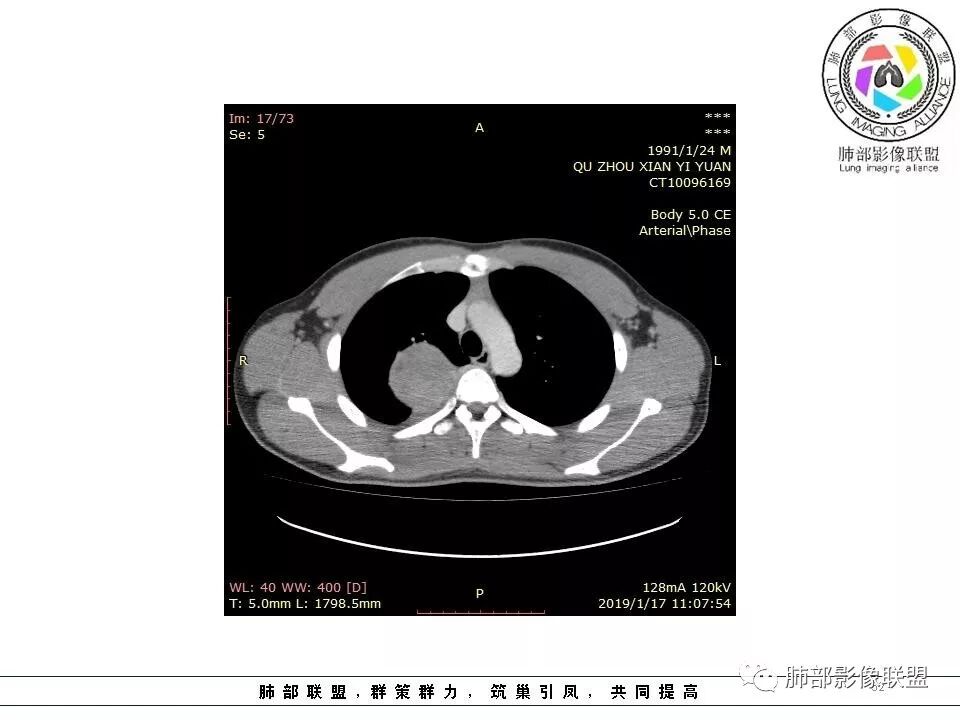

右后纵膈脊柱旁软组织占位,形态规则类圆,边缘光整,肺组织受压,胸膜尾,肋间动脉供血。中度不均匀延迟强化。

后纵隔脊柱旁占位性病变,疾病谱有神经鞘瘤,sft,节细胞瘤,髓外造血。此例有胸膜尾征,蛇纹征 ,延迟强化。考虑胸膜孤立性纤维瘤。看到有供血动脉,但不知道是哪里的血管。

右后纵膈脊柱旁软组织影,与纵隔结构分界不清,形态规则类圆,边缘光整,肺组织受压,胸膜尾,肋间动脉供血。肺动脉推移,中度不均匀延迟强化。考虑神经来源,神经鞘瘤,神经纤维瘤二者不易鉴别。

青年男性,间断胸痛;右侧脊柱旁可见一类圆形软组织密度影,密度欠均匀,增强扫描呈轻中度持续强化,邻近肺组织及肺动脉推移,可见肋间动脉供血,部分胸膜下脂肪可见,部分层面似见与右侧椎间孔相连。考虑后纵隔神经源性肿瘤。

病灶定位脏层胸膜,肺组织受挤压,有胸膜尾征,动脉期可见血管支配,考虑肺动脉供血,静脉期,强化增强明显,符合快进慢出特点,病灶内可见低密度区,考虑胸膜孤立纤维瘤。

右侧后纵隔脊柱旁占位,边缘光滑清晰,内侧肺组织受压,外侧可见胸膜尾征,增强持续强化,并可见蛇纹血管征。考虑SFT

青年男性,间断胸痛。右后纵膈脊柱旁软组织占位,形态规则类圆,边缘光整,肺组织受压,D字征,胸膜尾,肋间动脉供血。中度不均匀延迟强化。无支气管进入考虑来源于肺外、肿块与脊柱间未见明显脂肪间隙,考虑来源于胸膜外,考虑神经源性肿瘤,建议穿刺活检。

青年男性,右侧脊柱旁软组织肿块,边缘膨隆,密度不均,临近肺组织受压、胸膜增厚,增强后动脉期呈不均匀强化,并可见肋间动脉供血,延迟期强化较均匀,定位肺外,首先考虑SFT,神经源性肿瘤待排

青年男性,右侧后纵膈肿块,有胸膜尾征,支气管被推压,定位肺外,脏胸膜?血供来自肺动脉及肋间动脉,增强后有强化,蛇纹征,考虑SFT,鉴别鞘瘤

右肺占位,跨越上叶后段、下叶背,边缘光滑,瘤肺界面清,见肺压缩缘(线样不张`强化),见胸膜尾征,胸膜下脂肪未见明显增厚,肋骨丶脊柱未见侵袭及受压,渐进性丶地图样强化,冠状位似见体循环供血

诊断:SFT(来源壁层胸膜?一般小于20%)

鉴别:神经源性(鞘瘤)、LCD、肉瘤丶孤立性间皮瘤

右侧后纵膈肿块,有胸膜尾征,周围肺组织及支气管被推压,定位肺外,脏层胸膜来源,血供来自肺动脉或者支气管动脉,增强后持续渐进强化,蛇纹征,考虑SFT,鉴别鞘瘤。

青年男性,右后上纵隔脊柱旁沟可见团状软组织影,边界清,密度尚均匀,推挤邻近肺组织,胸膜可见掀起,有肺动脉供血,增强轻度蛇皮样强化,纵隔淋巴结未见肿大,邻近骨质未见破坏,胸膜下脂肪间隙消失,考虑SFT孤立性纤维瘤可能性大,鉴别神经鞘瘤,节细胞瘤,建议活检。

青年男性,胸痛,右上纵膈脊柱旁肿块,形态光整规则,支气管被推移,临近的胸膜明显增厚,有胸膜掀起,增强后密度不均匀,可见蛇形血管征,血供似乎有两根血管供血,考虑SFT

右后纵膈肿块,肺瘤界面清楚,胸膜尾征,邻近肺组织及支气管被推移,部分脂肪间隙存在,定位肺外来源,血供来自肋间动脉,增强后持续渐进强化,蛇纹征,考虑SFT,鞘瘤肿块内血管罕见,不考虑。

右上肺野脊柱旁软组织肿块,边缘光滑整齐,肺组织及气管右肺上叶支气管受压前移,外移,边缘可见胸膜尾征,病灶内密度不均,增强后渐进性持续强化,其内可见明显蛇纹血管征,首先考虑肺外来源,sft.可能性大

青年男性,右侧脊柱旁占位,瘤肺界限清晰,支气管推移,胸膜尾,D字征,胸膜下脂肪影,蛇纹血管,双重供血,延迟强化,定位胸膜,支持sft

病例小结

1.右上胸内脊柱旁类圆形肿块,质地似乎比较坚实,密度稍显不均,但未显示明确的坏死。

如此密度形态的病灶位于肺边缘首先应当想到孤立性纤维瘤,可相邻胸膜未见明显的异常强化和胸膜方向延伸。

注意所谓“胸膜尾征”的概念及形成机制与“脑膜尾征”是大不相同的。

2.肋间动脉病供血也提示肿块来自后纵隔?

3.相邻椎间孔未见扩大,也未见块影延入椎管,易起自于神经根的鞘瘤似乎找不到支持点。

可惜未提供矢状位骨窗图像,如在肋骨内下缘观察到压迹有助于肋间神经的鞘瘤的判断,这是因为二者之间密切的毗邻关系。

4.静脉期轻度不均匀强化,注意不是环形强化,亦未见明确的“AB区”,这点也不支持神经鞘瘤。临床及病灶轻度强化都不支持副节瘤。

尽管神经纤维瘤的诊断确实有些出乎意外,但病例开阔了我们的视野。